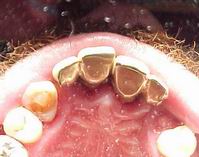

Munhões personalizados sobre modelo VISTA OCLUSAL

Prótese metalocerâmica personalizada VISTA OCLUSAL